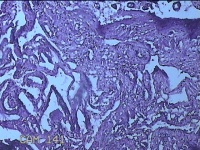

胎盘组织

性别

女

年龄

30岁

临床诊断

妊娠合并中度贫血

一般病史

停经39+2周,B超检查发现羊水偏少6小时。

标本名称

大体所见

灰白暗红色胎盘组织16.5x14.5x3.5㎝一个,表面光滑,血管突出,颜色发暗,绒毛面结节状,有轻度糜烂,暗红色,有少许凝血块,切面见绒毛内有暗红色血液渗出,边缘蜕膜可见多个小血肿,脐带39x1.8x0.3㎝,螺旋状扭曲,切断脐带,见脐血管内有凝血块。